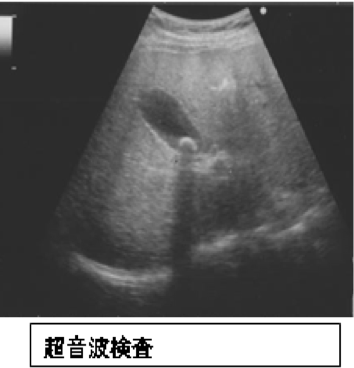

- 超音波検査(腹部エコー)

体への負担が少なく、胆石の有無や位置、胆嚢の状態を調べるための第一選択の検査です。多くの場合、この検査で診断が可能です。 - CT・MRI検査